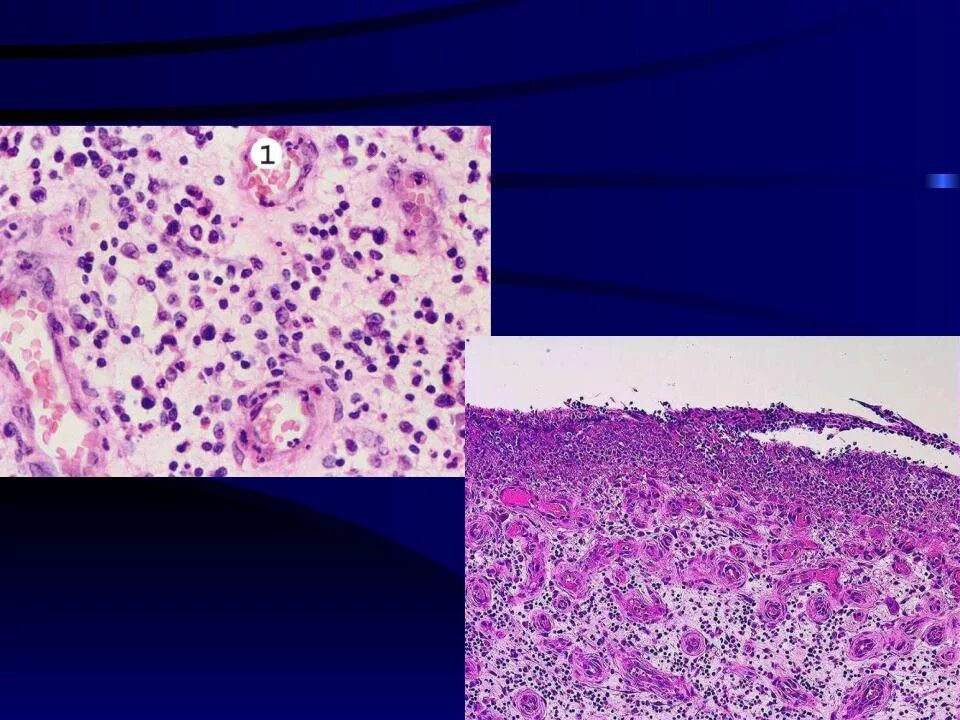

Регенерация тканей гистология